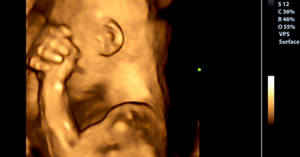

Tiede on osoittanut, että raskauden aikana vauva tuntee kohdussa samat asiat kuin äiti, ja samalla intensiteetillä. Jos siis itket surusta, vauvasi tulee kokemaan saman tunteen – hän kokee tämän surun ja tuskan omakseen.

Se, mitä vauvasi kokee vatsasi sisällä, on siis suoraan yhteydessä siihen, mitä sinulle itsellesi tapahtuu. Raskauden aikana olet hänelle kaikki kaikessa. Olet hänen lähin yhteytensä ulkopuoliseen maailmaan, ja olet myös hänen kohdunsisäinen maailmansa.

Raskauden aikana vauvasi valmistelee itseään elämään kohdun ulkopuolella, ja hän tekee tämän niiden viestien avulla, jotka sinä äitinä hänelle lähetät. Näin sanoo Curt A. Sandman, joka on yksi tieteilijöistä, jotka osallistuivat erääseen viimeaikaiseen tutkimukseen University of California-Irvine -yliopistossa. Tämä tutkimus osoittaa, että äidin tunne-elämän tila vaikuttaa hänen vauvansa kehitykseen ennen ja jälkeen syntymää.

Kyseinen tutkimus myös kertoo, että kun vauva on äidin kohdussa, se on aktiivinen osallistuja omassa kehityksessään. Tämä on erityisen totta siksi, että tänä aikana vauva kerää tietoa syntymän jälkeistä elämää varten.

Yksi kaikkein hienoimmista tämän tutkimuksen oivalluksista on se, että vauvat voivat myös tuntea ja kokea äitinsä tunne-elämän tilan.